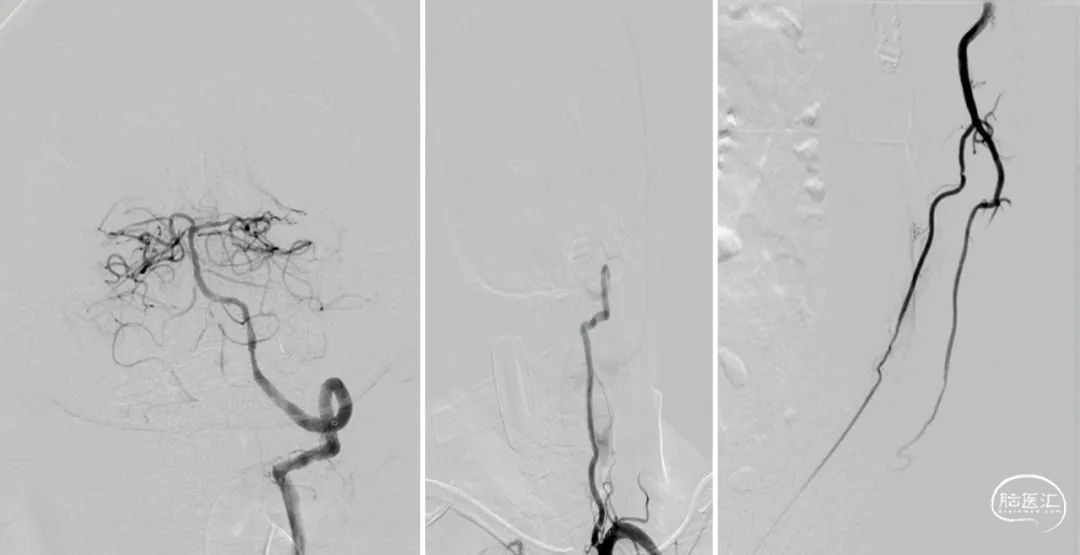

Tethys®中间导引导管沿导丝顺利到达病变近端附近,锁骨下至椎动脉转弯处充分体现了近端良好的⽀撑性与抗折性,帮助后续⾎管开通治疗建⽴稳定通路系统

中间导管到位后造影

微导丝通过狭窄段

微导丝置于左侧大脑后

球囊到位

3mm*20mm球囊扩张

复查造影

5min后复查造影